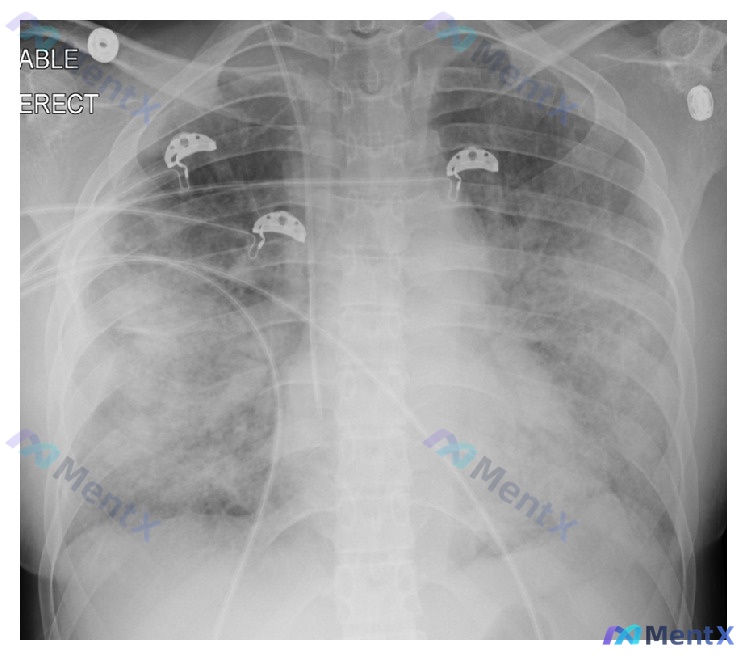

影像表现(胸片)

- 双肺弥漫性斑片状、云絮状高密度影,双侧中下肺野尤著,有融合趋势,肺野透亮度普遍降低(接近“白肺”)

- 心影轮廓似有增大,但边界欠清

- 可见中心静脉导管、心电监护电极/导联线

- 气管居中,无明显骨质破坏